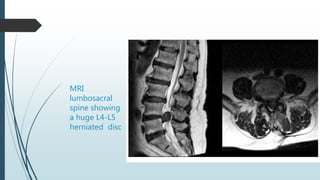

MRI

lumbosacral

spine showing

a huge L4-L5

herniated disc